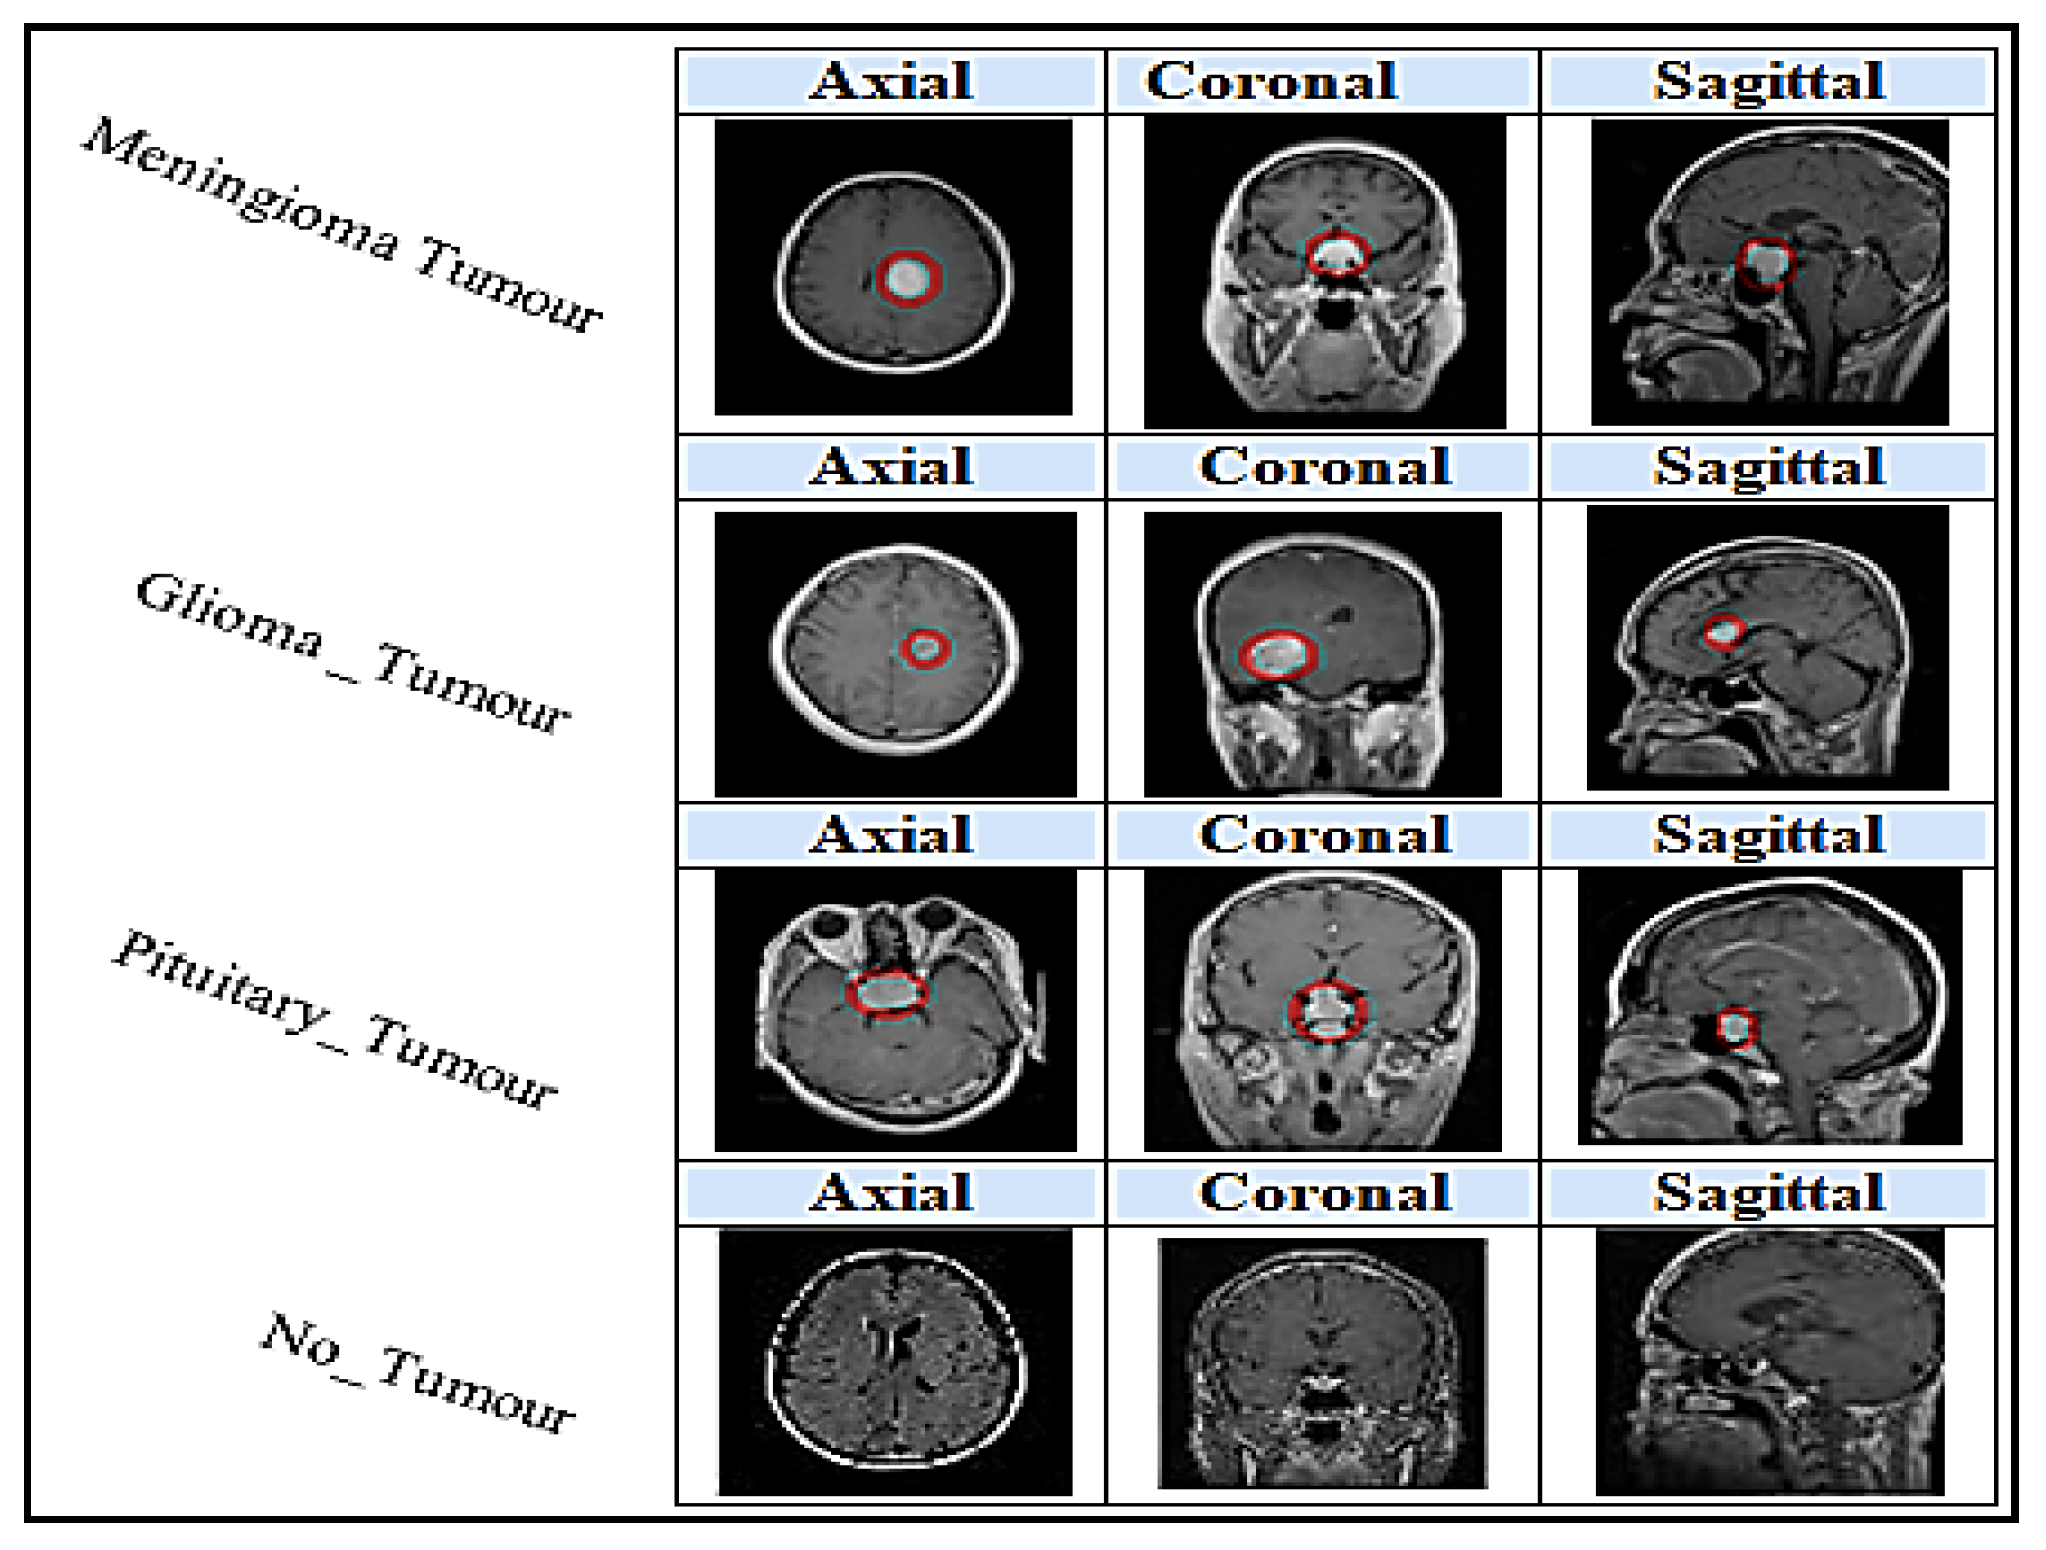

4.1. Dataset